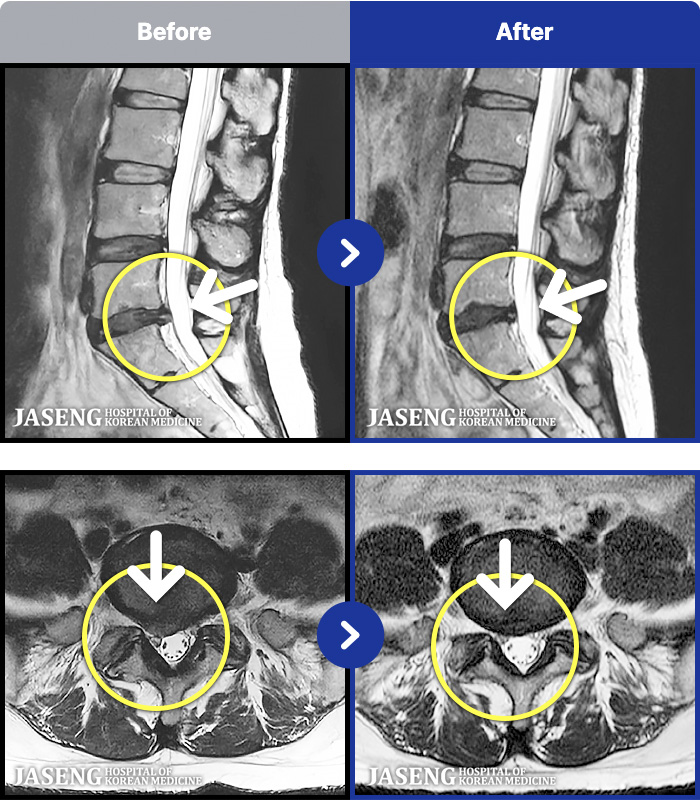

MRI ġ

1,237 MRI ũ ʸ Ȯϼ.